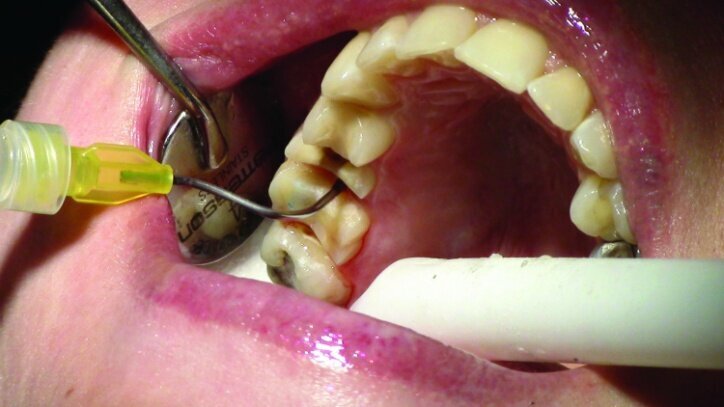

This patient presented for restorations of teeth #3 and #4 (Fig. 1a). Because of the size of the existing restorations, these teeth were diagnosed as structurally compromised (Figs. 1b, c). The prognosis without treatment was fair.

Local anesthesia was achieved with 1.7 cc 2 per cent Lidocaine with 1:100,000 epi, buffered with Onset sodium bicarbonate inj., 8.4 per cent, USP neutralizing additive solution.